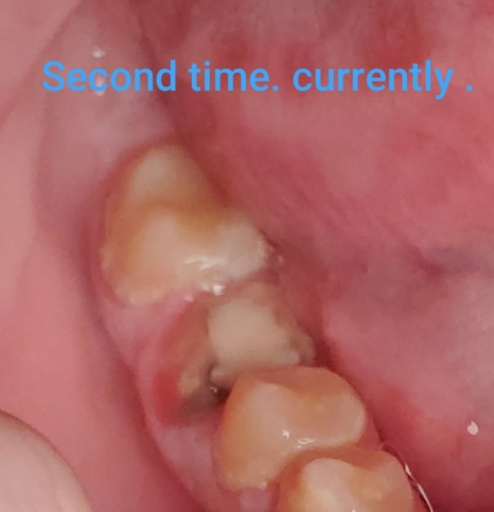

hi , i need an advise about my left lower molar tooth. I got a root canal done about 2 years ago and placed the crown couple weeks ago ( porcelain fused to high noble metal ) . Since i got this crown my tooth started to hurt when i was chewing food on it , i called my dentist and he found that crown is too high so he removed a bit of it but the problem is still existing . Now I started to feel the pain when brushing the tooth ( the gym hurts around it). also when I press with my finger the gym it hurts too. Today i went to my dentist again and informed him about the issues and he looked at it and thinks that the crown is ok only the problem is the gym and he took out a food that was in the gym around ( it was very painful and bleeding ) . Also i can't do the regular flossing because i can't get to this area with my hands its too far , so my dentist suggested me to buy a proxy brush for it . Do you think this kind of problem sounds like the gym issue or the problem is with the tooth itself and i should visit another dentist ? the last x-ray was 2 month ado and doctor sad everything is fine . before the crown was places this tooth and gym around never made any discomfort .